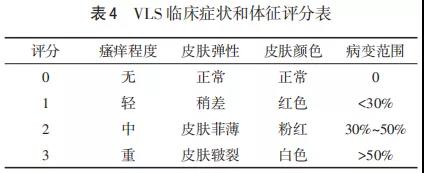

女性外阴硬化性苔藓(vulvar lichen sclerosus,VLS)是一种常见的外阴慢性炎症性非瘤样皮肤病变。本病以外阴及肛周的皮肤和黏膜萎缩变薄为主要特...